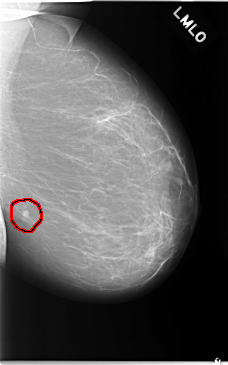

C_0042_1.LEFT_MLO

LEFT_MLO LINES 5840 PIXELS_PER_LINE 3648 BITS_PER_PIXEL 12 RESOLUTION 50 OVERLAY

FILE: C_0042_1.LEFT_MLO.OVERLAY

TOTAL_ABNORMALITIES 1

ABNORMALITY 1

LESION_TYPE MASS SHAPE IRREGULAR MARGINS SPICULATED

ASSESSMENT 5

SUBTLETY 5

PATHOLOGY MALIGNANT

TOTAL_OUTLINES 1

BOUNDARY